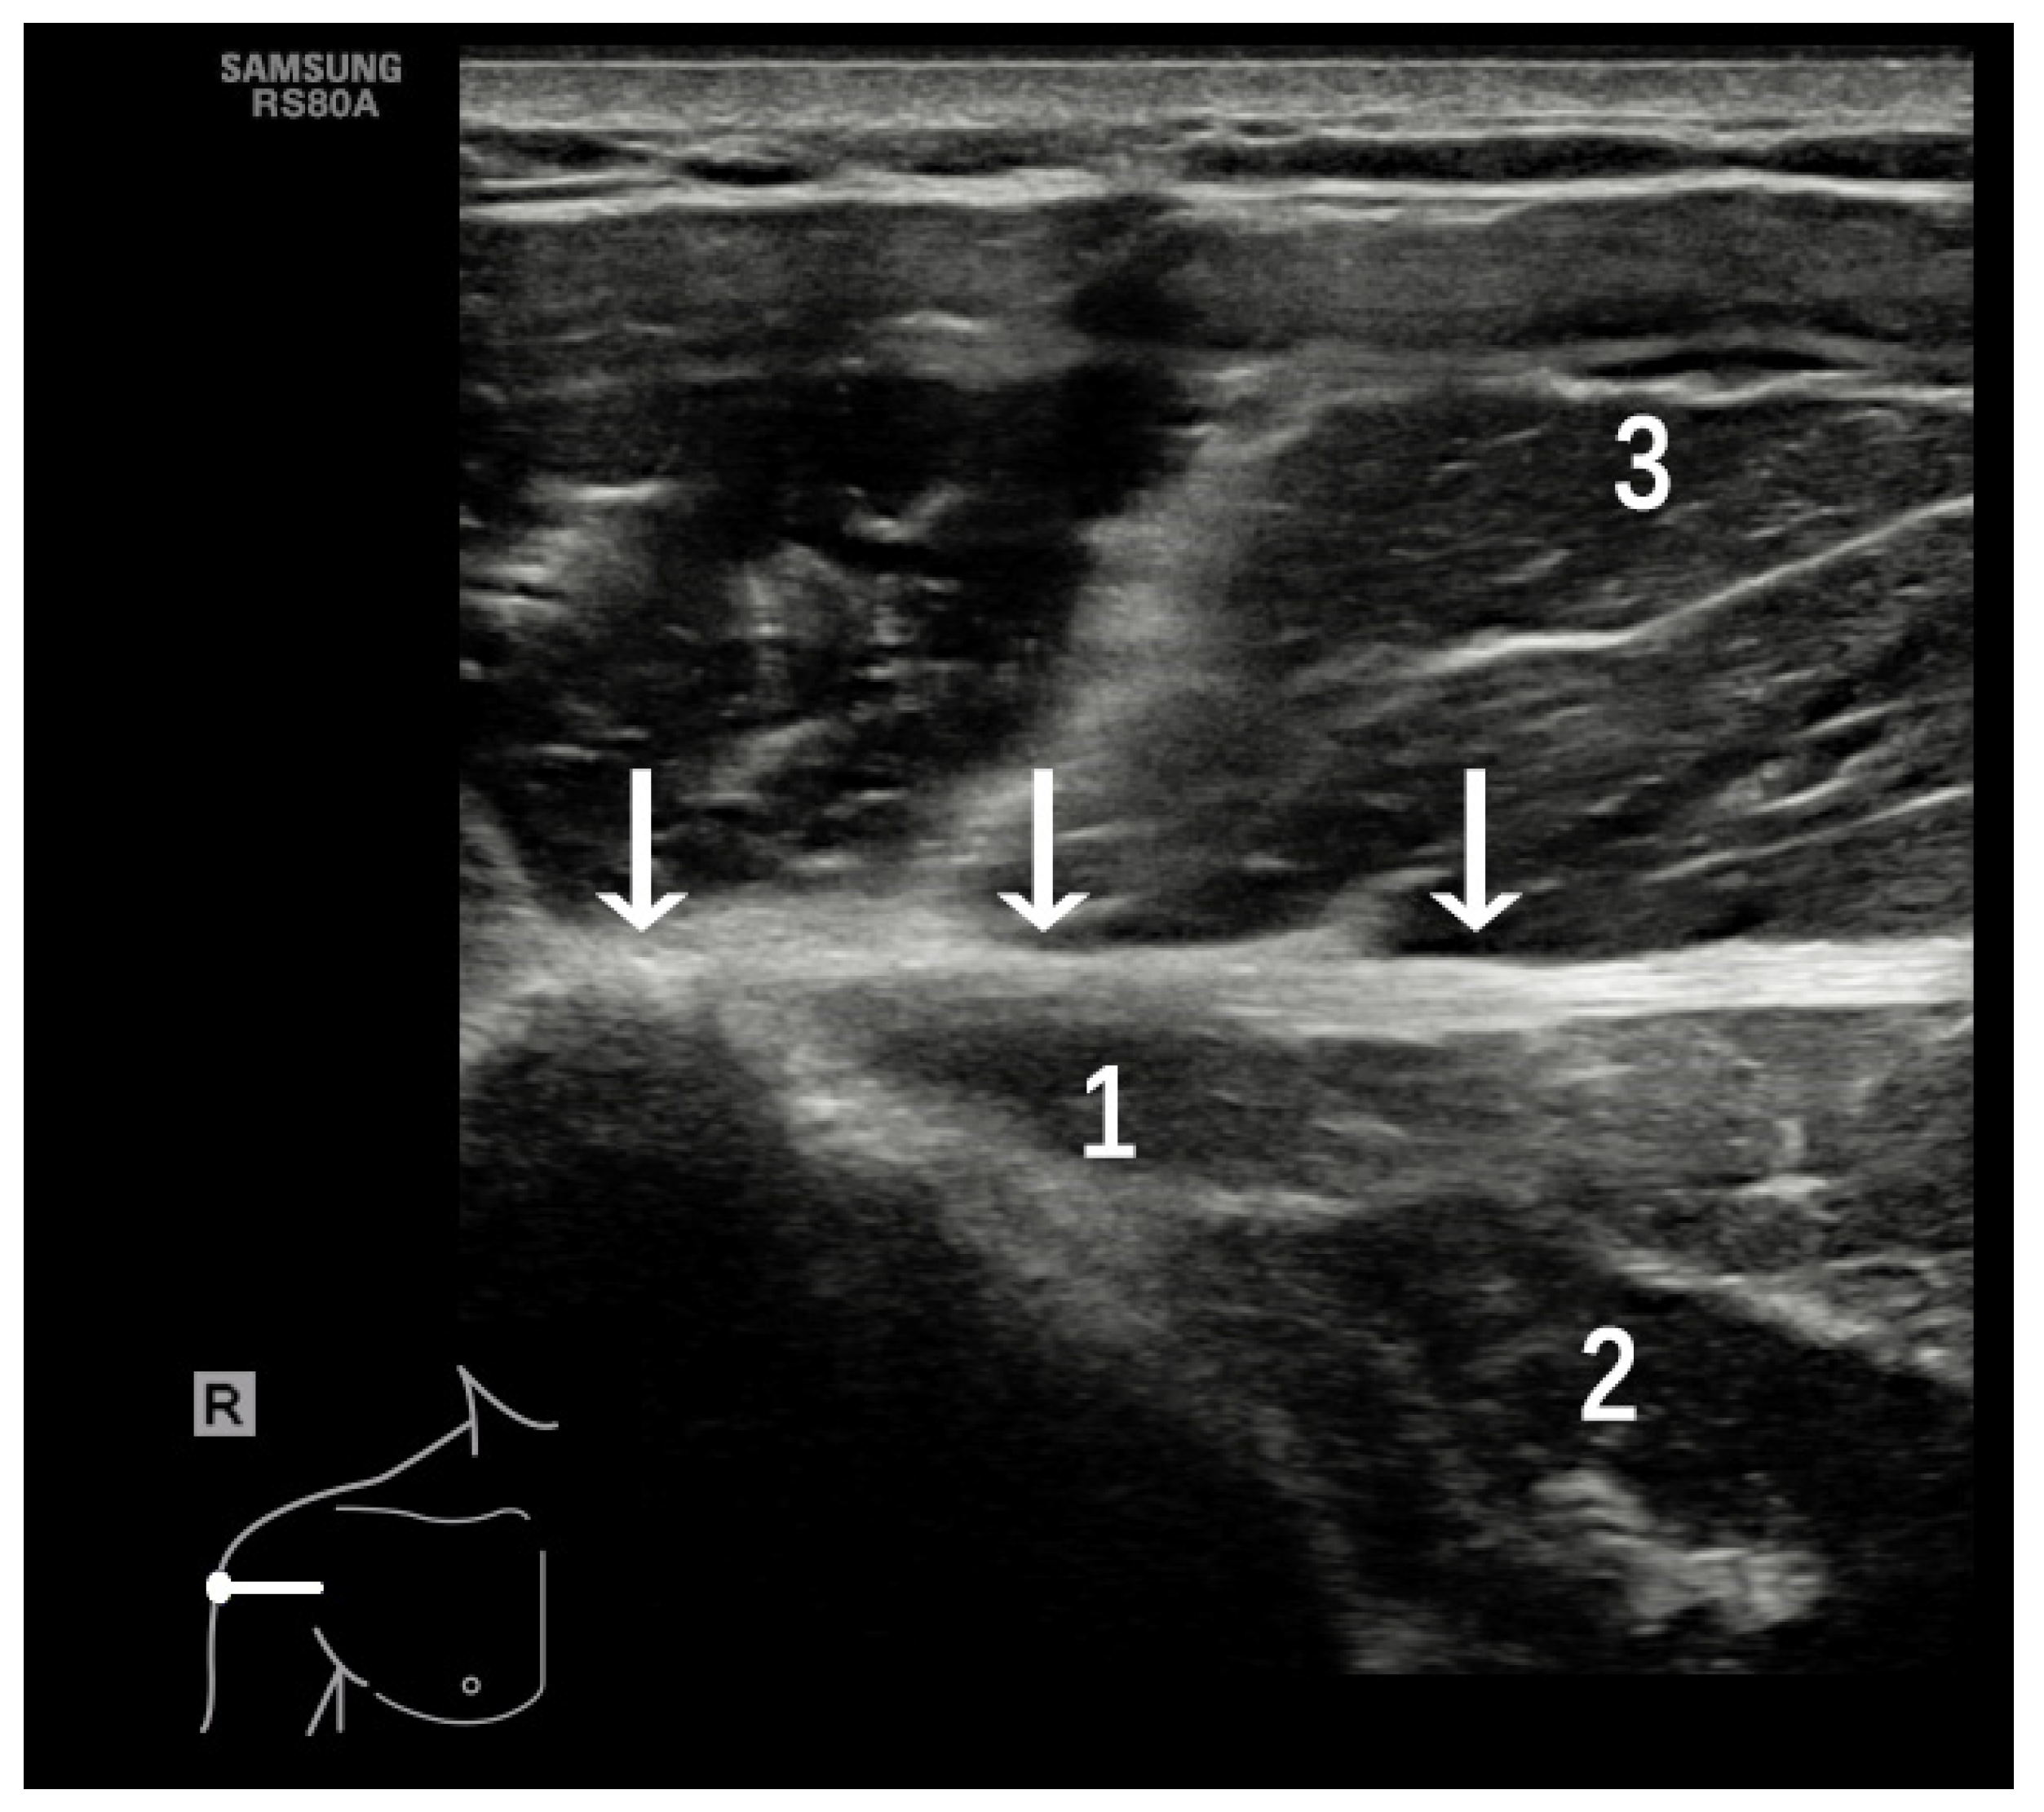

4.2. Adhesive Capsulitis (AC)

4.3. Chronic Pathology of the SSC and SSP Tendons

4.4. PM Tendon Tears